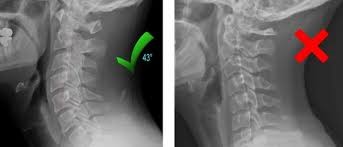

Servikal Omurga için ideal Eğri Nedir?

Sağlıklı bir servikal omurga, genellikle hafif bir yay şeklindedir ve konveksliği boynun arkasına doğru bakar. Bu eğrilik genellikle derece cinsinden ifade edilir ve normal aralık yaklaşık 20-40 derecedir. Ancak, “normal”in kişiden kişiye değişebileceğini unutmamak önemlidir.

Hipolordoz ve Hiperlordoz

Boyun eğriliğinin azalması (hipo-lordoz) veya fazla artması(hiper-lordoz) sorunlarına yol açabilir. Boyundaki bu değişiklikler kötü duruş, omurga yaralanmaları veya doğuştan omurga rahatsızlıkları gibi faktörlerden kaynaklanabilir.